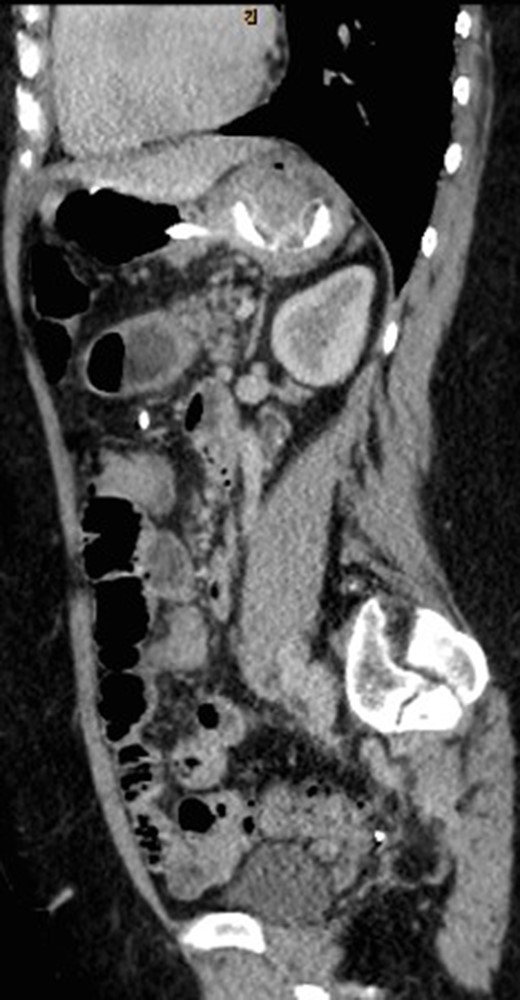

CT abdomen with oral and intravenous contrast was organized to further investigate the tubular foreign body. It revealed concurrent gastric band erosion into gastric lumen and connection tubing eroding into the posterior wall of transverse colon and exiting inferiorly (Figs 2–6). There was no evidence of any oral contrast leak from the stomach.

Sagittal view of CT abdomen showing the gastric band tubing eroding into posterior wall of transverse colon and exiting inferiorly.